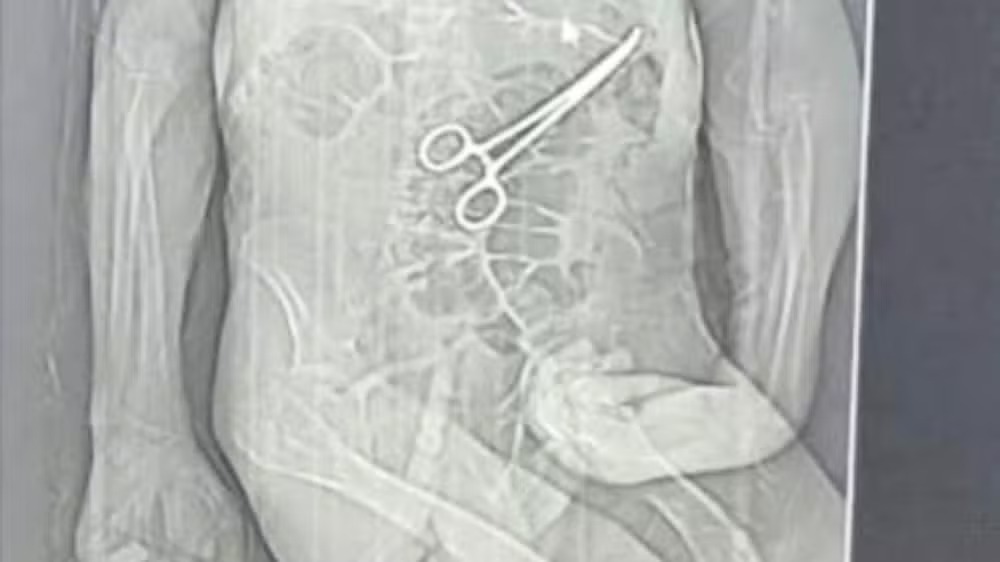

Tomografia mostrou pinça cirúrgica dentro do corpo do idoso (Foto: Rádio Nova FM/Reprodução)

Logo após a morte do aposentado, uma rádio local teve acesso a um exame de tomografia que indicaria a presença de um instrumento cirúrgico dentro do corpo do paciente. A família informou que acompanha as apurações e vai requisitar os prontuários, laudos e exames clínicos feitos no hospital.